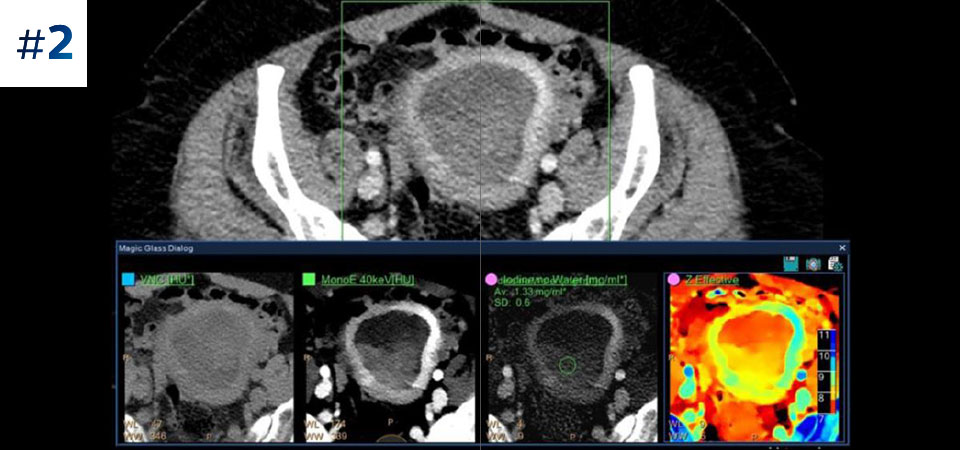

Reduced follow-up exams Improved tissue characterization and visualization may reduce the need for follow-up scanning for sub-optimal exams and incidental findings.

See the difference between spectral-detector CT and conventional CT

Learn about the advantages of spectral-detector CT